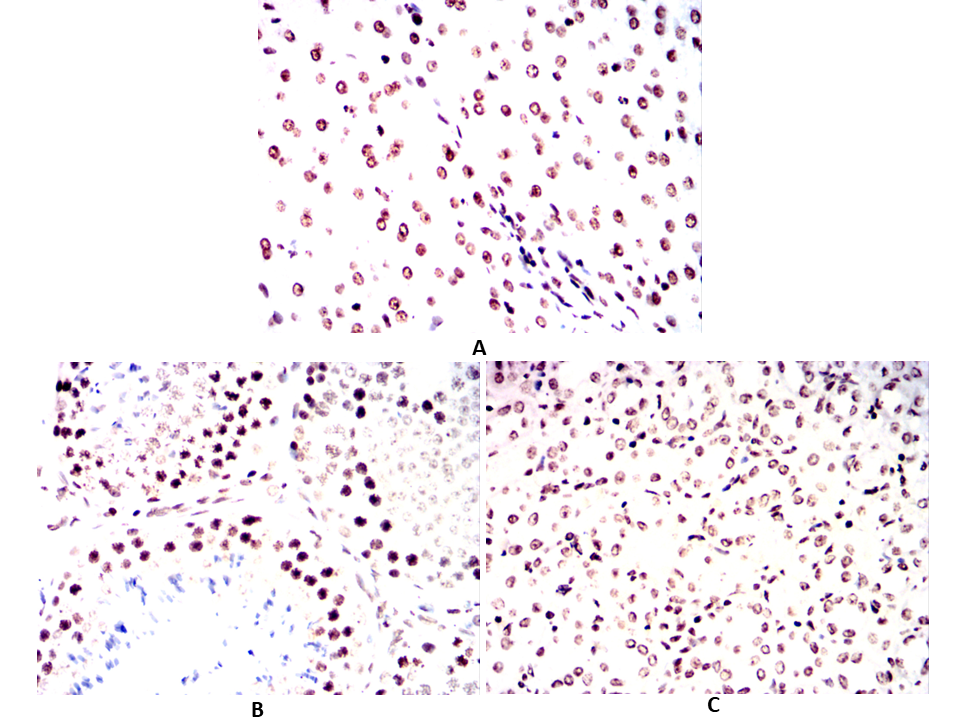

| IHC | 1/100 - 1/500 | Human,Mouse,Rat,Rabbit |

Antibodies targeting p16 are essential tools in both research and diagnostics. Mouse- and human-specific p16 antibodies enable the detection of p16 expression across species, facilitating comparative studies in preclinical models (e.g., murine systems) and human tissues. These antibodies are widely used in techniques such as immunohistochemistry (IHC), Western blotting, and immunofluorescence to assess p16 status in tumors, senescent cells, or disease models. In clinical settings, p16 immunohistochemistry serves as a surrogate marker for high-risk human papillomavirus (HPV) infection in cervical and head/neck cancers, aiding diagnosis and prognosis.